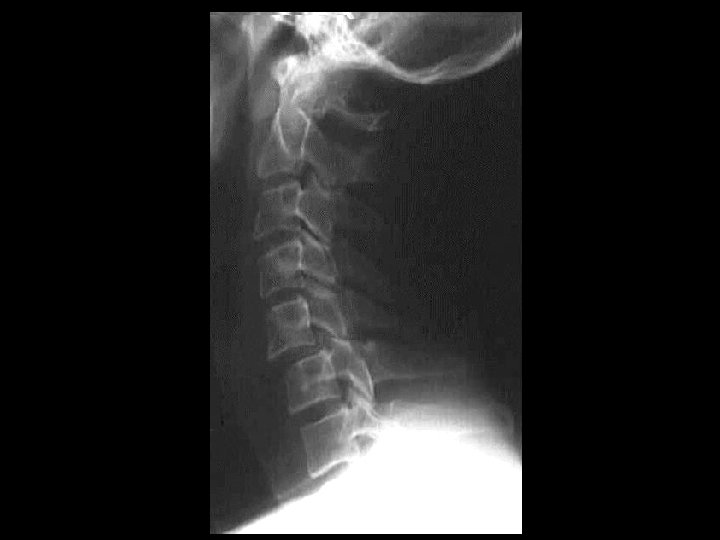

Atlantooccipital dislocation Findings anterior and superior displacement of

Atlanto-occipital dislocation • Findings: – anterior and superior displacement of occipital condyles in relation to C 1 – pre-vertebral soft tissue swelling – mechanism: hyperflexion or hyperextension – UNSTABLE